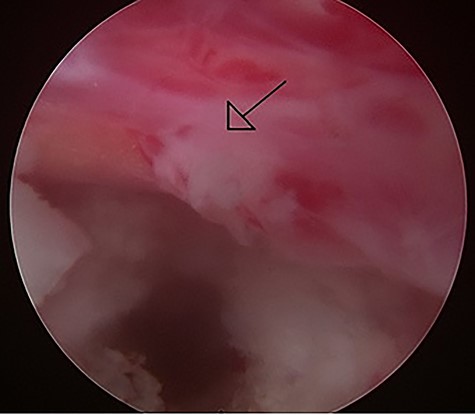

Intraoperative image of the percutaneous endoscopic interlaminar lumbar discectomy at the L5/S1 level left S1 root with hyperemic inflammation was noted after the protruding disc was removed.

During the operation, a bulging fragile disc with purulent debris was noted. After removal of the disc, the left S1 nerve root expanded well (Fig. 2). No obvious purulent fluid accumulation was noted. After the surgery, her left sciatica and low back pain improved. Her CRP also decreased to 0.69 mg/dl, and repeated blood cultures were negative for pathogens. Her intraoperative specimens did not reveal any pathogens on bacterial culture. Antibiotics with intravenous vancomycin had been given for 14 days and were shifted to oral amoxicillin upon discharge.